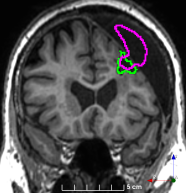

(f)

Figure 3: Manual labels from Rater A (green) and Rater D, the model trained with PubFull + EpiPre + Pseudo (magenta). Errors caused by a (a) small resection, (b) blood clot in cavity and (c) brain shift; segmentations corresponding to the (d) 50th, (e) 75th and (f) 100th percentiles giving a DSC of 81.7, 86.5 and 93.8, respectively.

We trained a model using PubFull, EpiPre and Pseudo (2371 images), obtaining a DSC of 81.7 (14.2). Adding the pseudo-labels to PubFull and EpiPre did not significantly improve performance (p=0.176𝑝0.176p=0.176), indicating our semi-supervised learning approach provided no advantage. Predictions from this model are shown in Fig. 3.

Predictions errors are mostly due to 1) resection of size comparable to sulci (Fig. 6a), 2) unanticipated intensities, such as those caused by the presence of blood clots in the cavity (Fig. 6b), 3) brain shift (Fig. 6c) and 4) white matter hypointensities (Fig. 6e). Further work will involve using different internal and external cavity textures, carefully sampling the resection volume, simulating brain shift using biomechanical models, and quantifying epistemic and aleatoric segmentation uncertainty to better assess model performance [24].